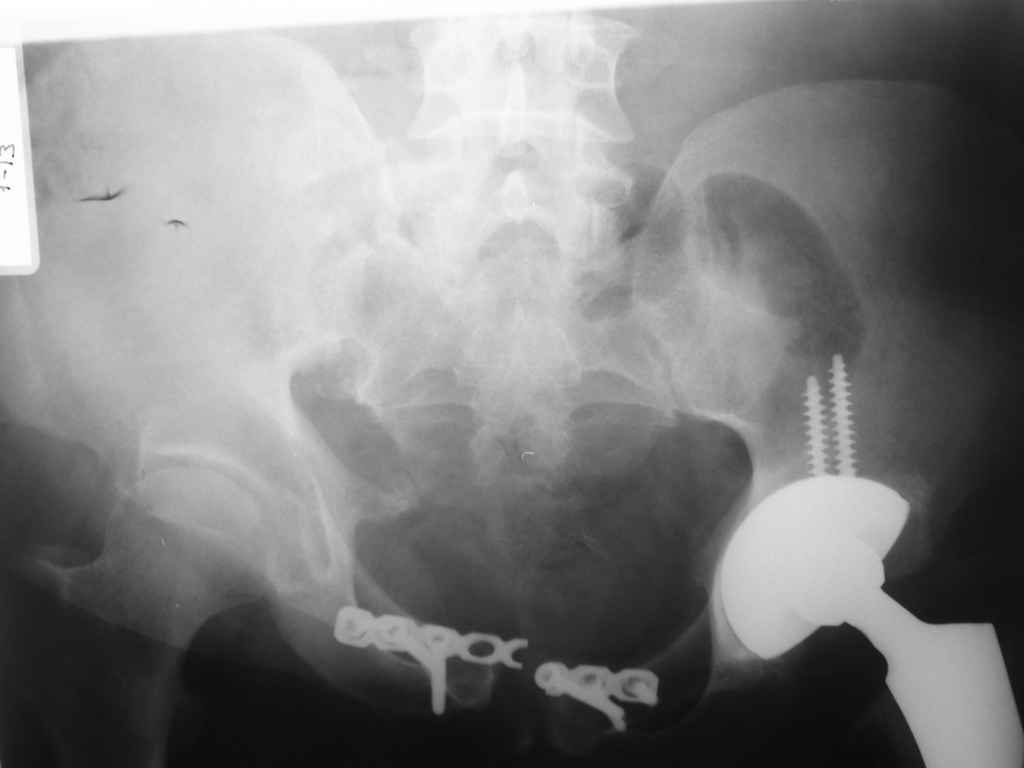

Несостоятельность лонной пластины связана с нестабильностью правого крестцово-подвздощного сочленения.

"Длина конечностей слева(+2см)" наверное имелось ввиду укорочение конечности, указывающее на смещение в ложном суставе КПС.

Передняя пластина на симфиз и дополнительный наружный фиксатор без фиксации заднего полукольца не создает эффективную фиксацию,

вследствие нестабильности таза быстро наступает несостоятельность передней пластины.

Дорогой Андрей. Мы имеем дело с комбинированной (ротационно и вертикально) нестабильностью таза со смещением правого гнемипелвиса. При таких переломах, фиксация только переднего полукольца вне зависимости от метода фиксации, как уже было сказано Djoldas Kuldjanov, M.D., не может создать адекватной фиксации. И перелом пластины был вполне ожидаемым после активизации пациента. Смещение сохраняется, и по-видимому не 2 см., а все 4, если не более. Разница всего (+2 см) по конечностям как вы указываете, скорее скомпенсировано позвоночником и протезом. Дополнительные снимки или КТ исследование помогли бы уточнить степень смещения с точностью до мм., выявить перелом поперечного отростка пятого поясничного позвонка, или помимо разрыва правого крестцово-подвздошного сочленения выявить перелом боковой массы крестца справа и т.д. При возможности, конечно, все это желательно сделать. Но мало что изменится с практической точки зрения, т.к. задача - это низведение репозиция и надежная фиксация правого гемипелвиса. Учитывая плачевный опыт стержневого аппарата, давность травмы совершенно очевидно, что поставленная задача достижима при открытой репозиции и одномоментной фиксации переднего полукольца с артродезированием правого крестцово-подвздошного сустава. Операция выполняется в положении больного на здоровом боку или полубоку из расширенного трансоссального подвздошно-пахового доступа с переходом на лонное сочленение доступом по Pfannenstiel. Указанный доступ обеспечивает подход к крестцово-подвздошному сочленению как спереди так и сзади. После артродезирования выполняется синтез лонного сочленения. Клинический пример

Пациентка С.26 лет. Травма за 6 месяцев до поступления

Укорочение правой нижней конечности до 10см

23.09.2003. Одновременный остеосинтез переднего и заднего тазовых полуколец

Результат через 10 дней

и 8месяцев после операции